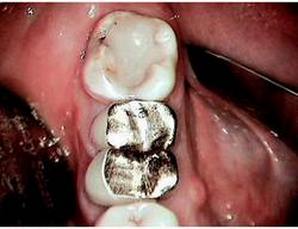

The implant offers an increase of $284 in gross production over the three-unit bridge, which is no big deal. However, you have provided a better and more permanent solution for your patient. Note that this example assumes that no extraction is needed, no site preservation is needed, there is good bone both vertically and horizontally, and adjacent teeth are not in need of restoration–essentially a perfect situation! This rarely presents itself in my practice. So, let’s consider a more realistic example, specifically the case that was presented pictorially in the last article. You may remember the “tired” molar that was failing with a fistula and hemisected roots. In that case, the patient would not entertain any removable solution, so I presented her with these fixed solutions for comparison:

Option 1: Traditional Three-Unit Bridge, $3,319 (including extraction at $121, two retainers at $1,000 each, pontic at $1,000, plus core build-up for distal retainer at $198). Option 2: Single Tooth Implant, $4,753 (including extraction at $121, site preservation $150, implant placement $1,822, abutment $462, crown $1,000; plus core build-up $198 and crown $1,000 to restore distal tooth).